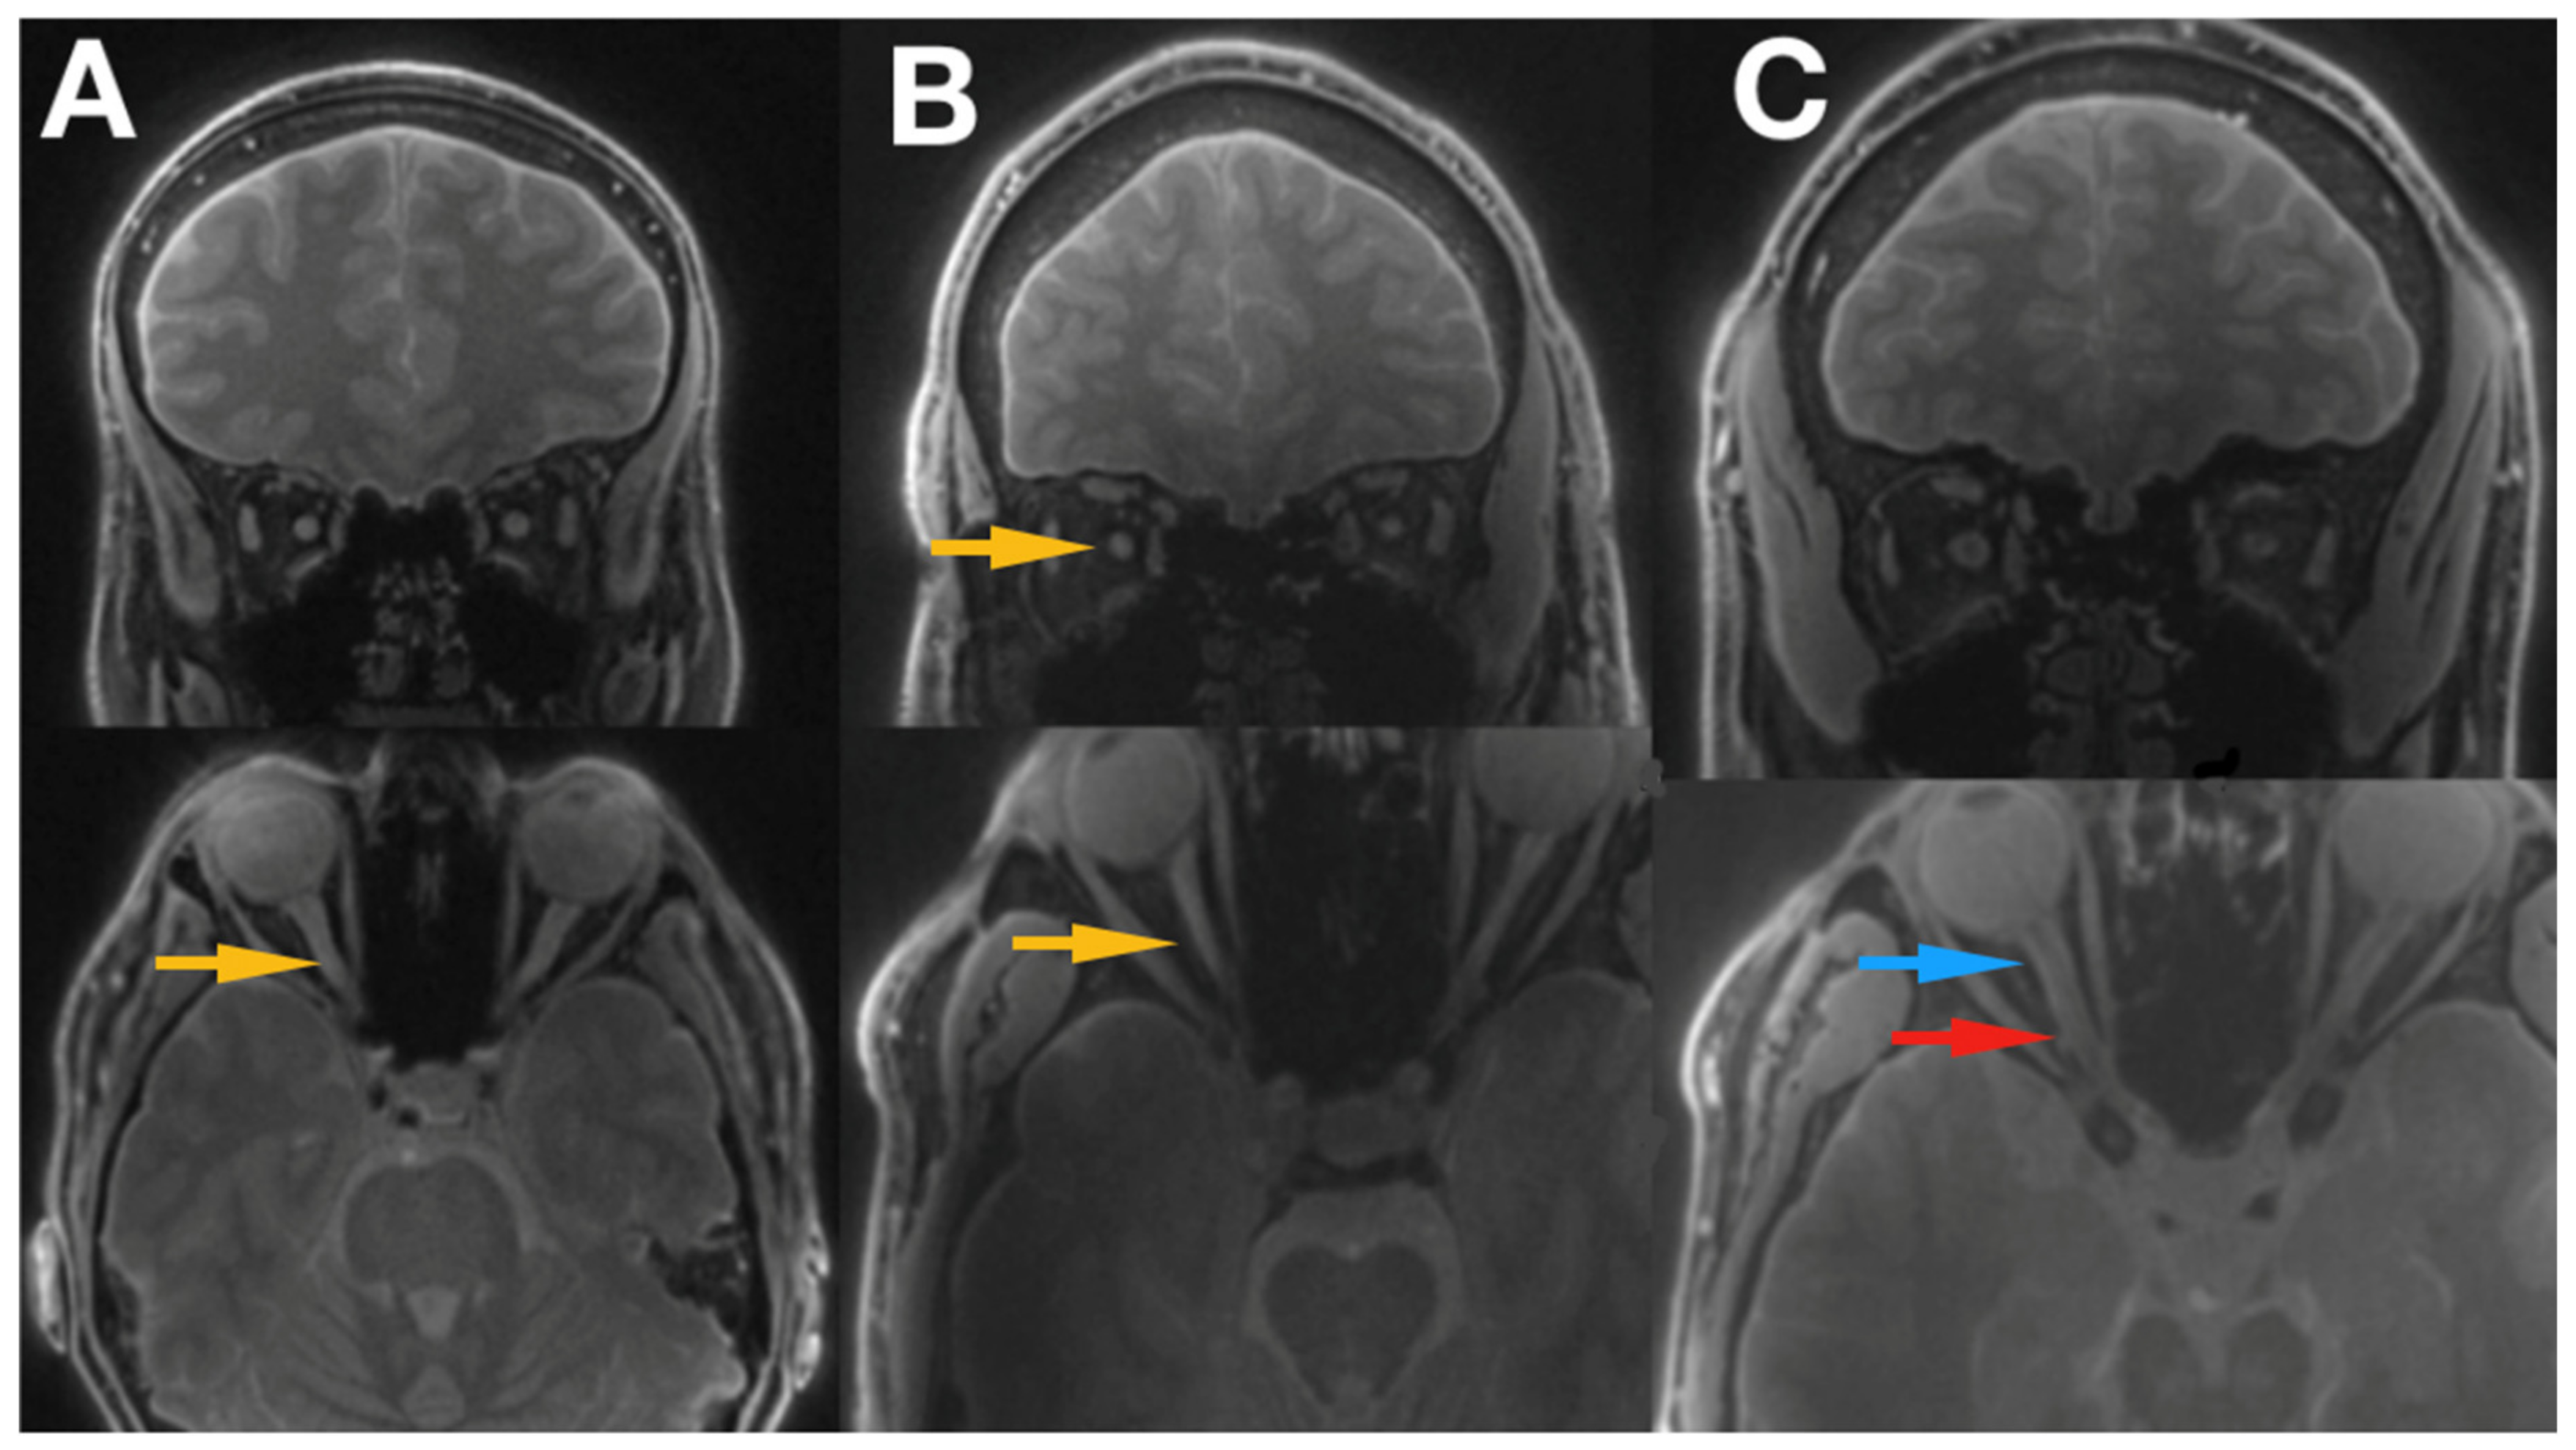

3.1. Radiological Inspection